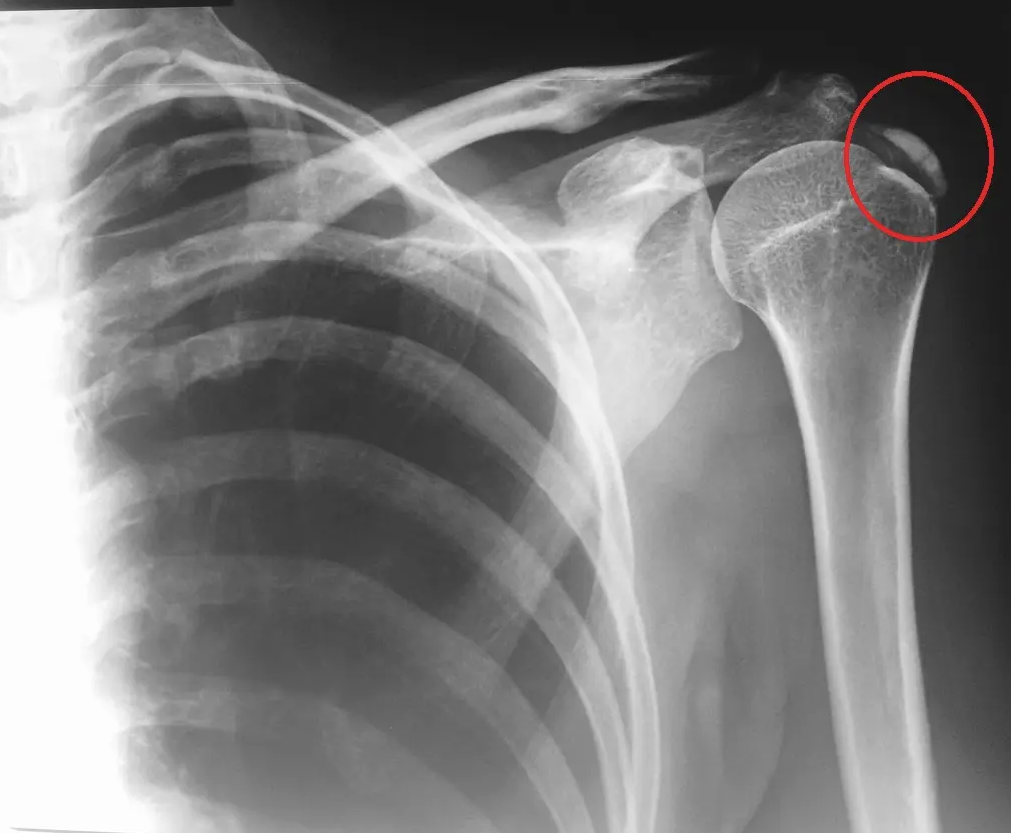

Snimka pojave kalficikata u ramenu

Za dodatnu dijagnostiku te procjenu veličine i karakteristika kalcifikata koristimo i radiološke-slikovne poput rendgena ramena, ultrazvuka, ponekad i magnetske rezonance (MR).